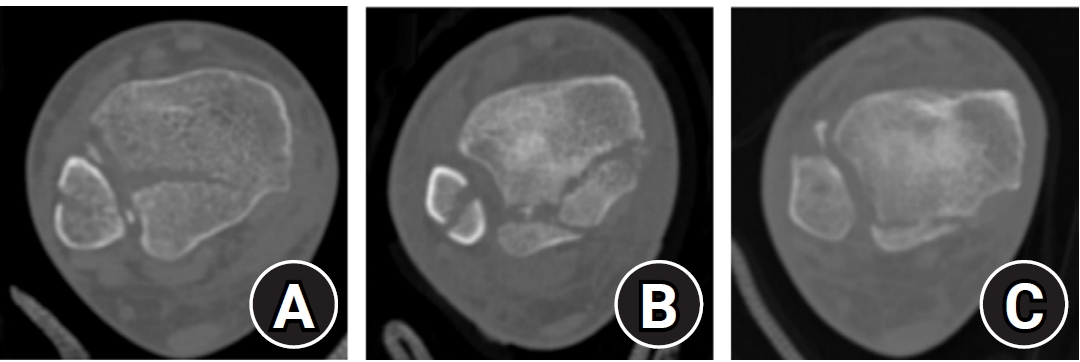

Posterior malleolar fracture morphology was classified according to the Haraguchi and Bartonicek systems (Figs. 2, 3) [19,20]. The peak height of the posterior malleolar fracture was measured as the vertical distance from the highest point of the distal tibial articular surface to the fracture apex in the sagittal plane (Fig. 4A). The articular surface area of the posterior malleolar fragment was calculated using the region of interest tool in a picture archiving and communication system (Maroview 5.4; INFINITT Healthcare) (Fig. 4B). All quantitative radiographic measurements were performed by two orthopedic surgeons; mean values were used. For categorical variables, disagreements were resolved by consensus.

Fig. 3.

Bartonicek classification of posterior malleolar fractures. (A) Type 1: extraincisural fragment with an intact fibular notch. (B) Type 2: posterolateral fragment extending into the fibular notch. (C) Type 3: posteromedial two-part fragment involving the medial malleolus. (D) Type 4: large posterolateral triangular fragment.

Fig. 3. Bartonicek classification of posterior malleolar fractures. (A) Type 1: extraincisural fragment with an intact fibular notch. (B) Type 2: posterolateral fragment extending into the fibular notch. (C) Type 3: posteromedial two-part fragment involving the medial malleolus. (D) Type 4: large posterolateral triangular fragment.